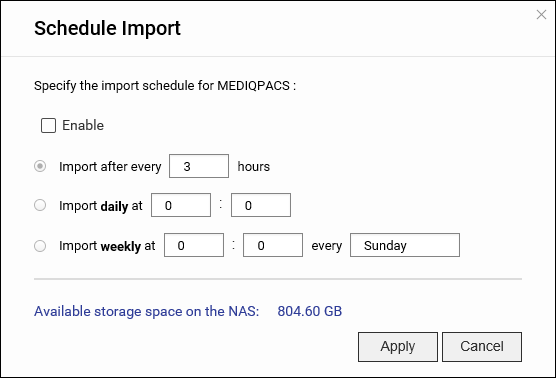

用户可按计划将 DICOM 图像导入到基于 NAS 的 PACS 服务器,也可以将它们直接导入。

自动导入图像